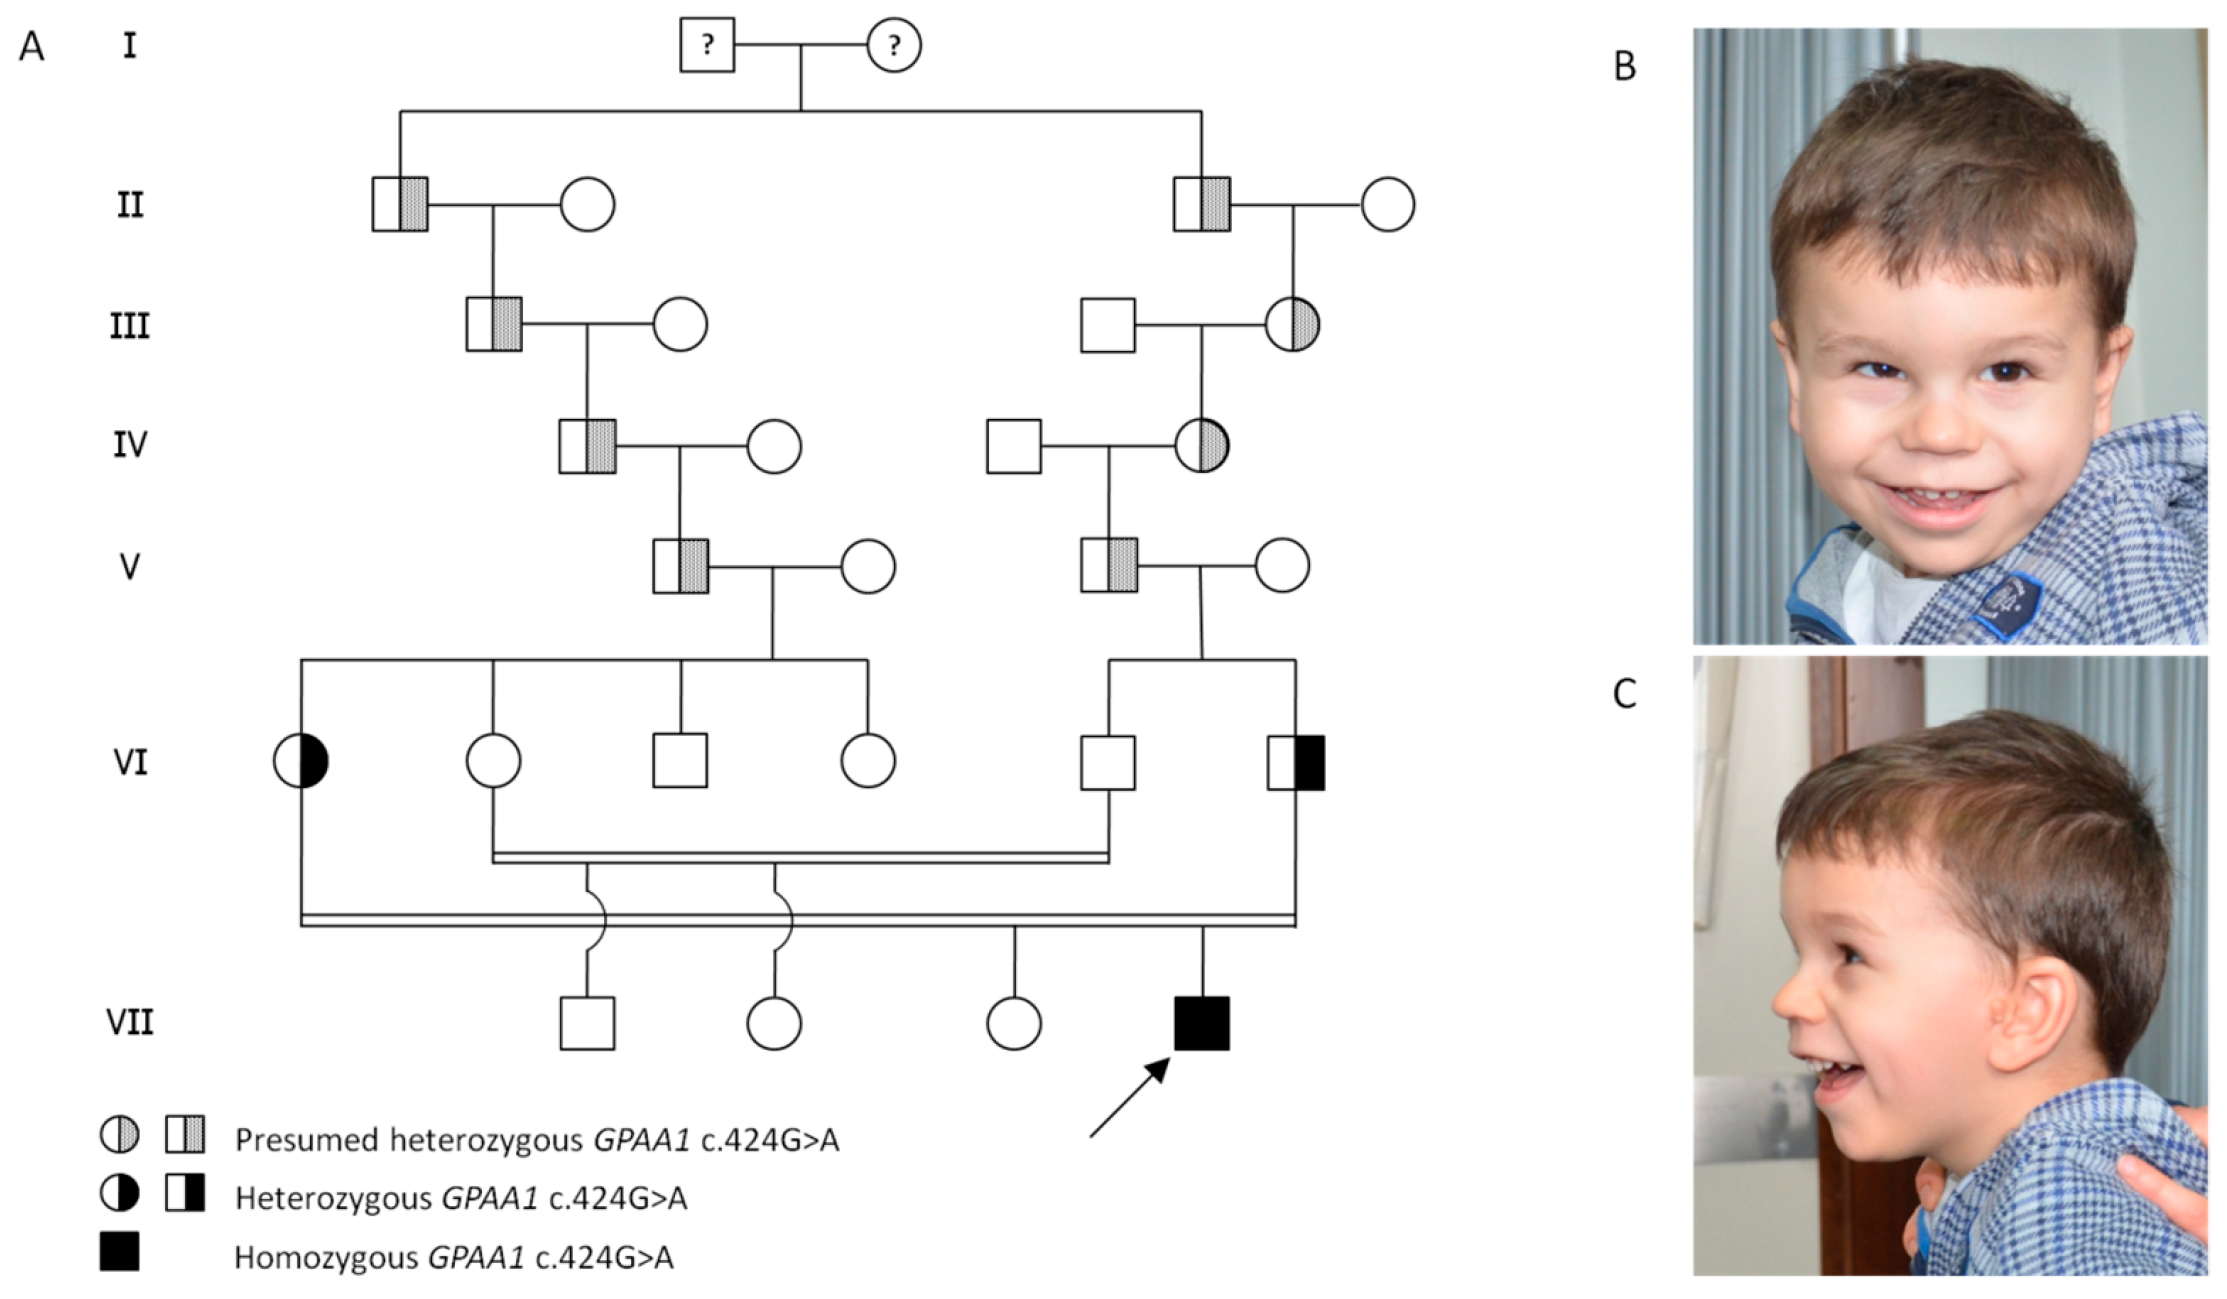

2. Clinical Report

4. Results